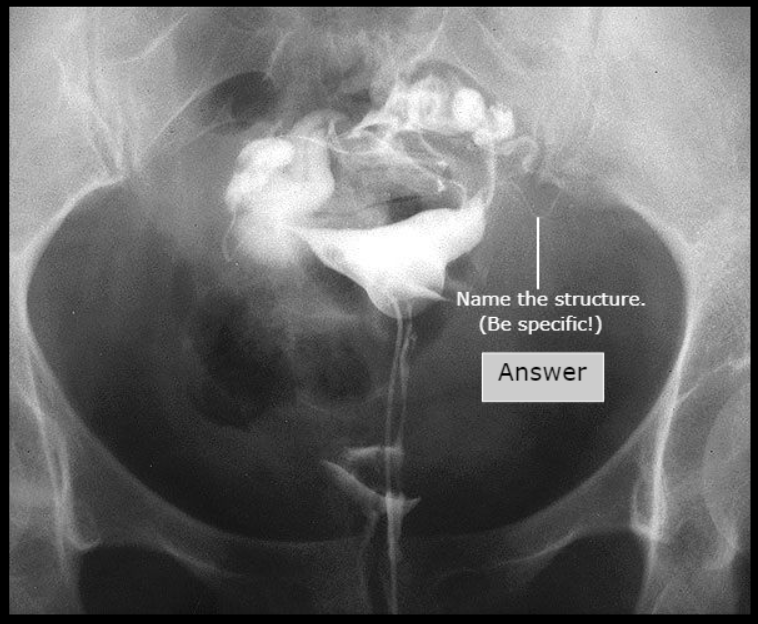

Prostatic Urethra